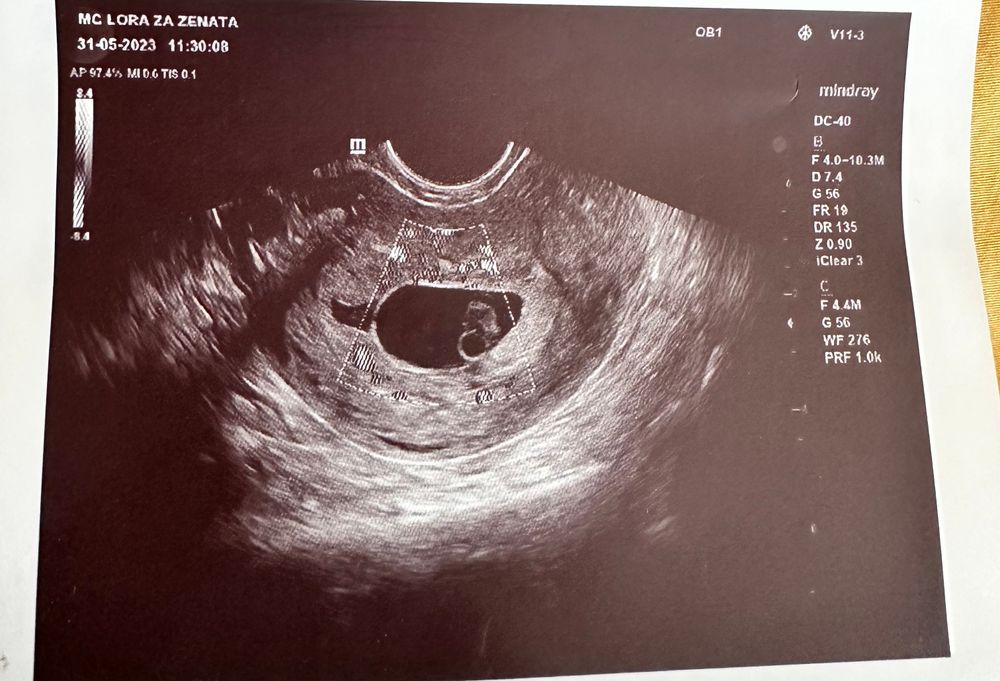

По узи кто разбирается? С/б еще нет

Не могу понять, почему не сб нет 😭 Может ли быть что была поздняя овуляция?

Скиньте протокол УЗИ,с описанием,по фото эмбрион уже приличный,сб должно быть,если я правильно поняла ктр 7,4,но с таким уже если нет сб,то зб ставят

Азалия, ну вы писали что вам по УЗИ поставили 6,5 недель,а по УЗИ срок ставят по размеру эмбриона и получается что эмбрион ваш ктр 7,4 мм как на фото,увы...но с таким уже должно быть сердцебиение,у меня ктр 5,4 мм был,сб 146 уд/мин,у девочек при ктр 3 мм сб есть,а у вас ещё и срок по месячным 8,5 недель,т.е даже если овуляция была в конце цикла позже на 2 недели,все равно сб должно быть,видимо замер на сроке 6,5

Желточный мешок есть. Эмбрион есть. Значит сб скоро появится. Думала у вас срок меньше, сейчас глянула. Если реально 9 недель,то возможно,зб или идите к другому врачу.

Нужно знать хотя бы размеры ПЯ , чтобы что-то сказать.Так по фото вроде большое пя и эмбрион , у которого должно уже было быть сб.

По узи тут не больше 7 недель. В 7 недель они как орешки кешью, но и сб конечно должно быть …